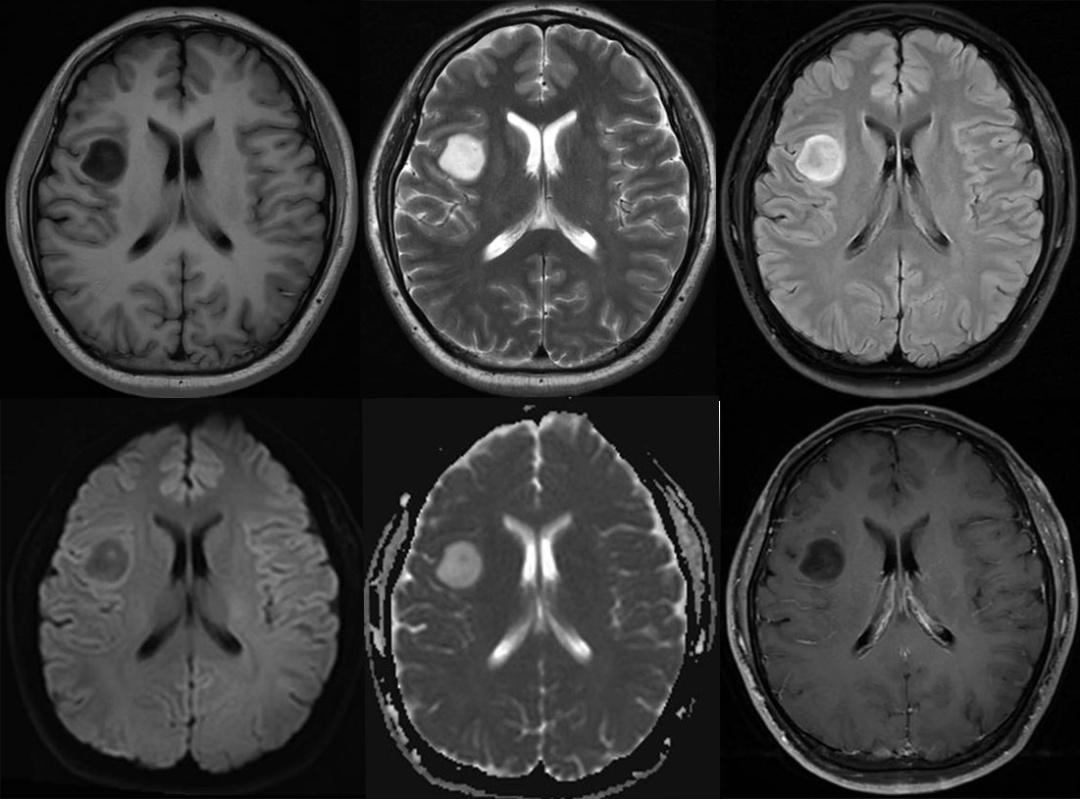

影像学检查:

T2-FLAIR

回过头看本病例,肿瘤在 T2WI 呈主体均质高信号,FLAIR 主体呈低信号,周围环形高信号;术后病理为星形细胞瘤 IDH 突变型。

2 例星形细胞瘤 IDH 突变型,均表现为 T2-FLAIR 错配,注意 FLAIR 低信号可以是均匀或不均匀